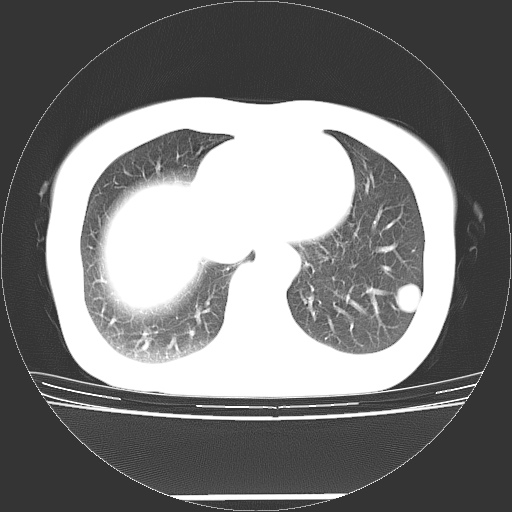

标题: CT27224:女,43岁,体检发现左肺下叶结节影。 [打印本页]

女,43岁,体检发现左肺下叶结节影。

左下肺外带胸膜下见孤立实性均匀密度结节影,边缘光整,增强呈渐进性强化,病灶吴分叶征及毛刺征象;支持硬化性血管瘤。

左肺下叶基底段圆形结节,多考虑:错构瘤>硬化性血瘤>炎症假瘤>周围性肺癌!期待结果!

左肺下叶外侧基底段圆形结节,多考虑:错构瘤>硬化性血瘤>炎症假瘤>周围性肺癌!期待结果!

良性结节,有钙化,强化不明显,考虑软骨性错构瘤。

左肺下叶外基底段良性结节(错构瘤?)。